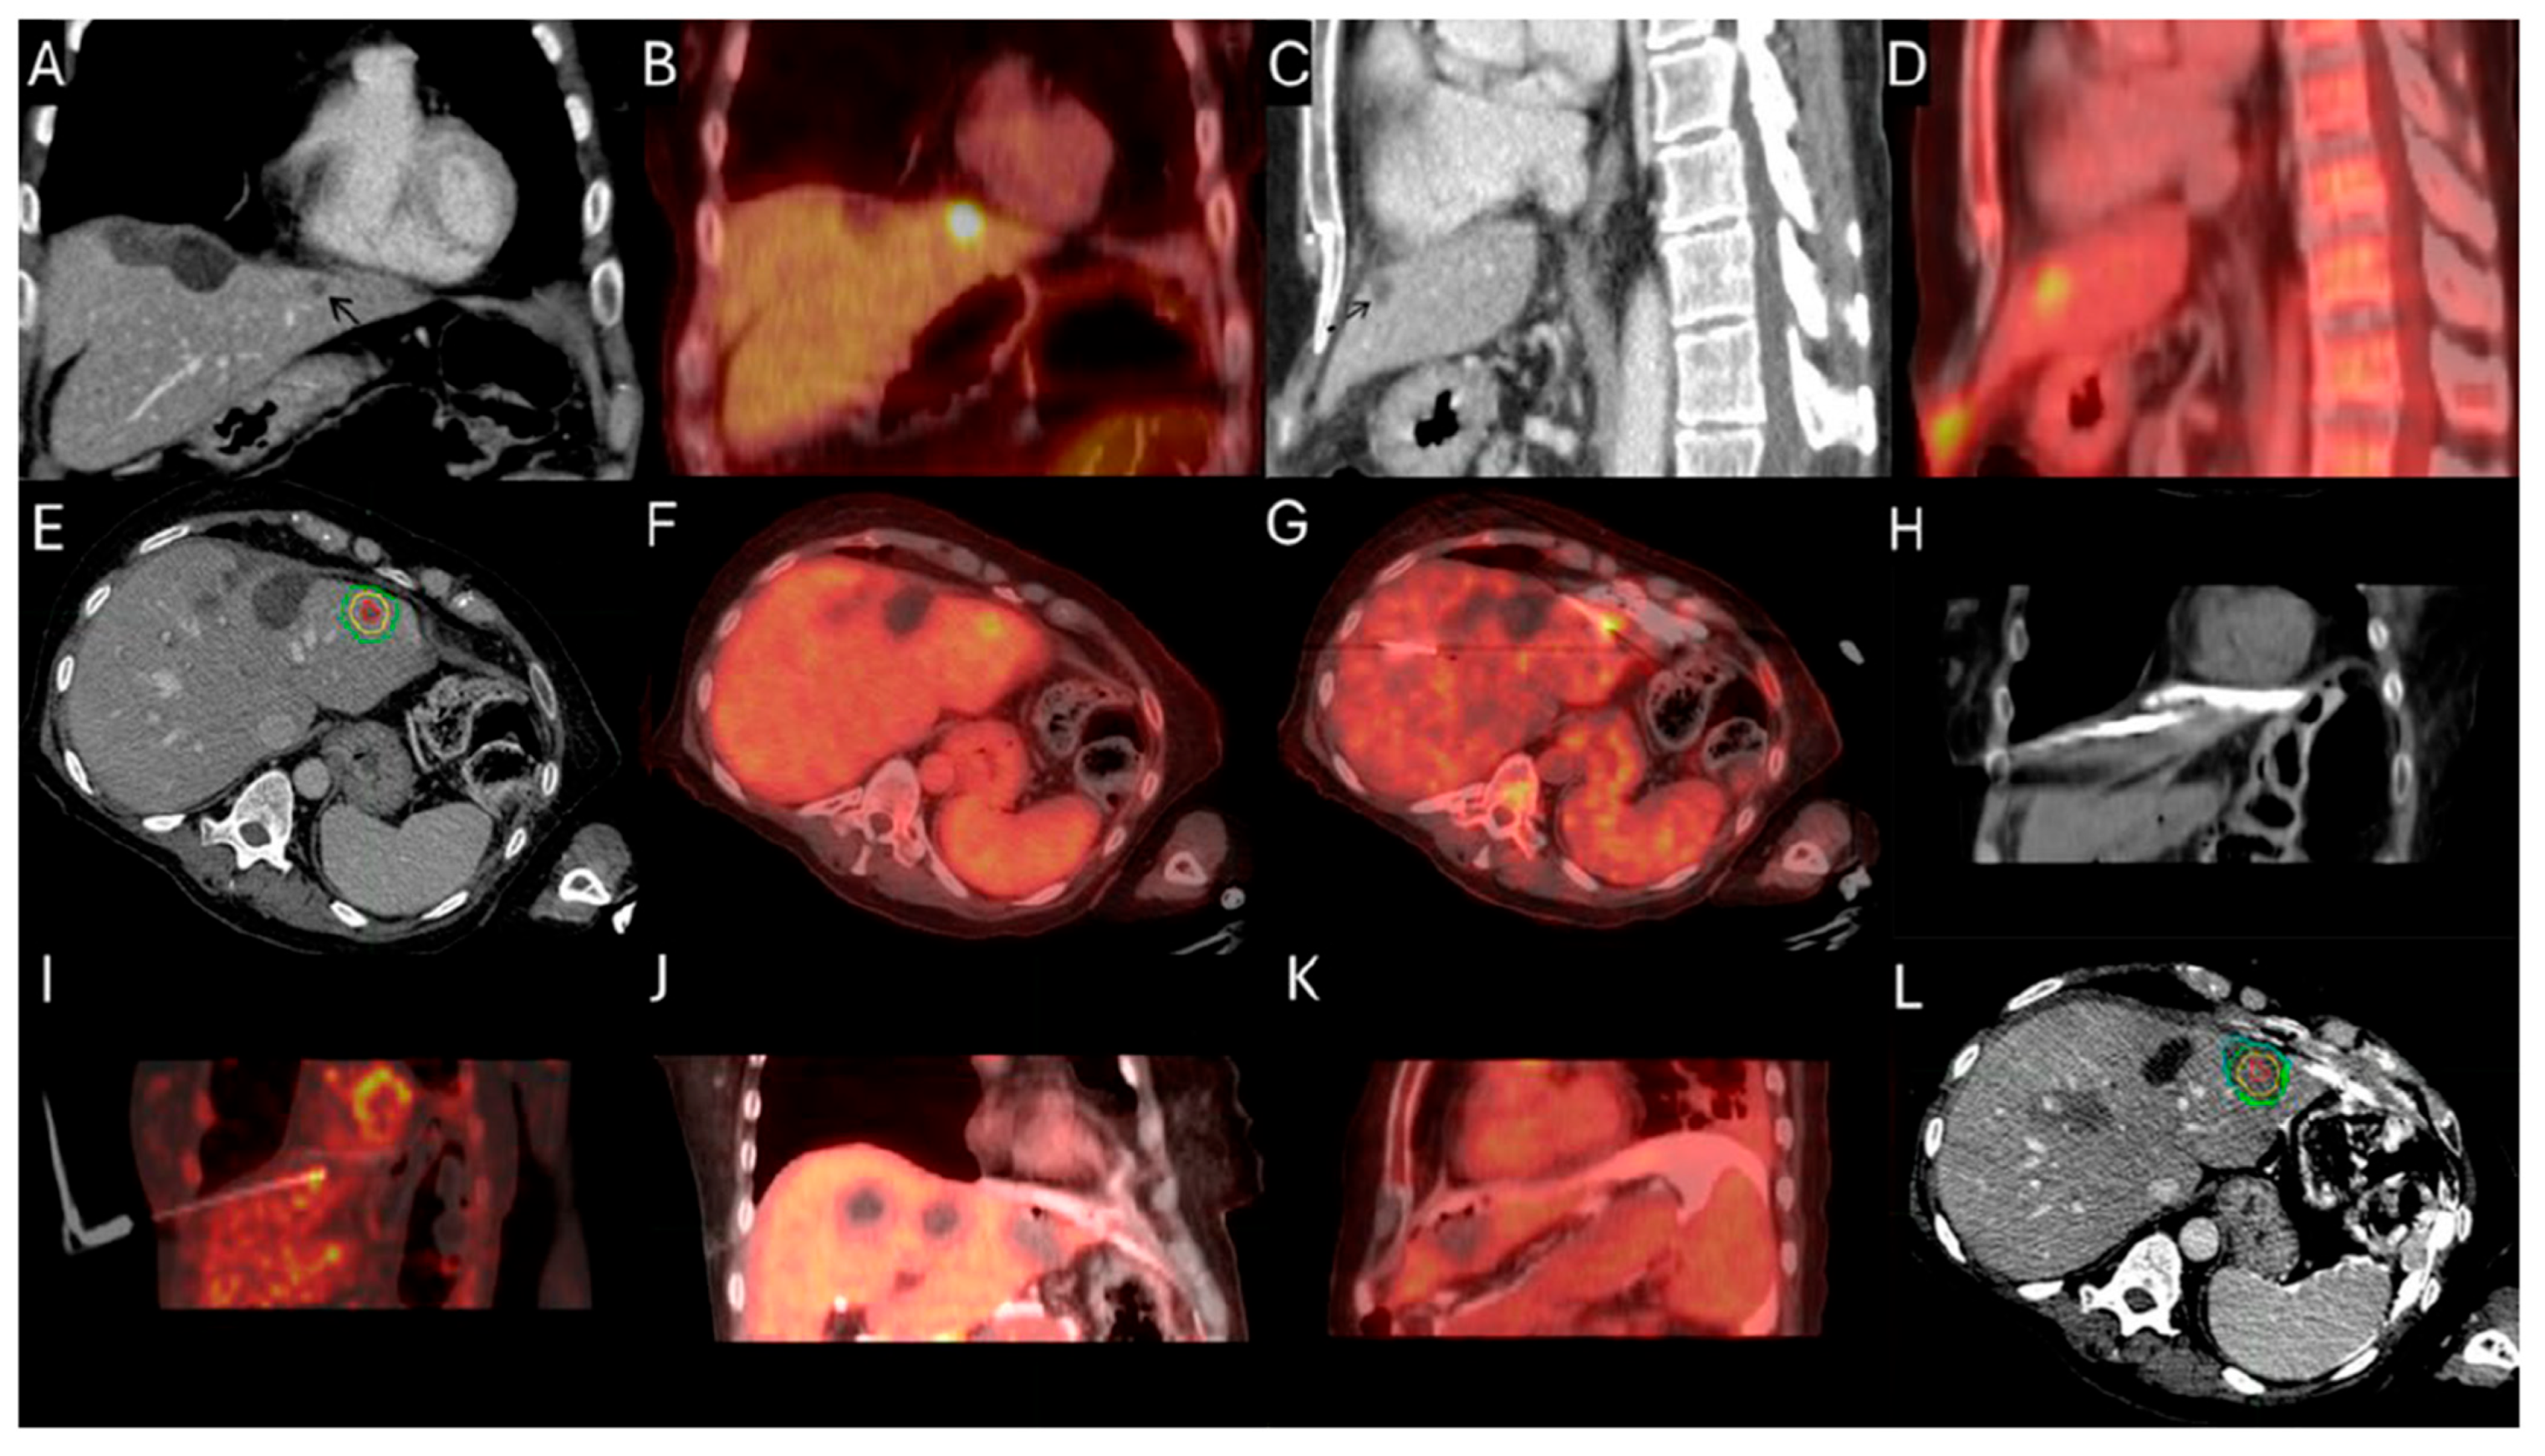

Figure 3.

63-year-old female with metastatic colorectal cancer liver dominant disease, previously treated with chemotherapy, hepatectomy, and intraoperative thermal ablations at segment 8, undergoes MWA for new colorectal liver metastasis (CLM) in segment 2. Pre-procedure ceCT ((A,C), black arrowhead) and FDG-PET (B,D) demonstrate the subdiaphragmatic metastasis in close proximity to the coronary sinus and the pericardium. MIM DEV version 3.3.7 semi-automatically generated target tumor and margin contours: using the intra-procedure pre-ablation ceCT, red circle represents the tumor contours, yellow and green circles represent the 5 and 10 mm (mm) margins around the target tumor, respectively (E). Administration of the first dose (4mCi) of FDG according to split-dose protocol provides clear visualization of the FDG-avid tumor (F). Extensive hydrodissection creates a buffer between the pericardium and the edge of the liver (G,H). Short acquisition 1 min breath-hold real-time FDG PET/CT scans confirm accurate placement of the microwave ablation electrode during hydrodissection (I). Second injection of 8mCi FDG confirms absence of residual metabolic activity (J,K). Post-ablation ceCT demonstrates the ablation zone (blue circle) uniformly covering in 3-dimension (3D) the tumor with 5 mm margins, confirming ablation completeness (L).